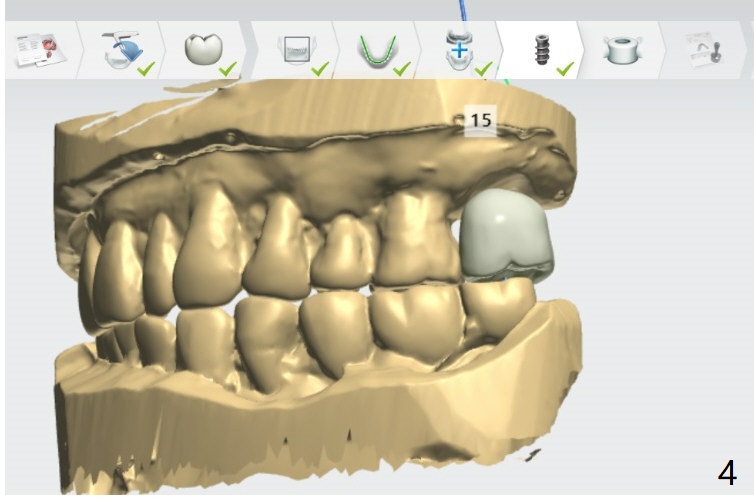

Return to Upper Molar Immediate Implant, Trajectory II

Xin Wei, DDS, PhD, MS 1st edition 01/31/2019, last revision 09/03/2019